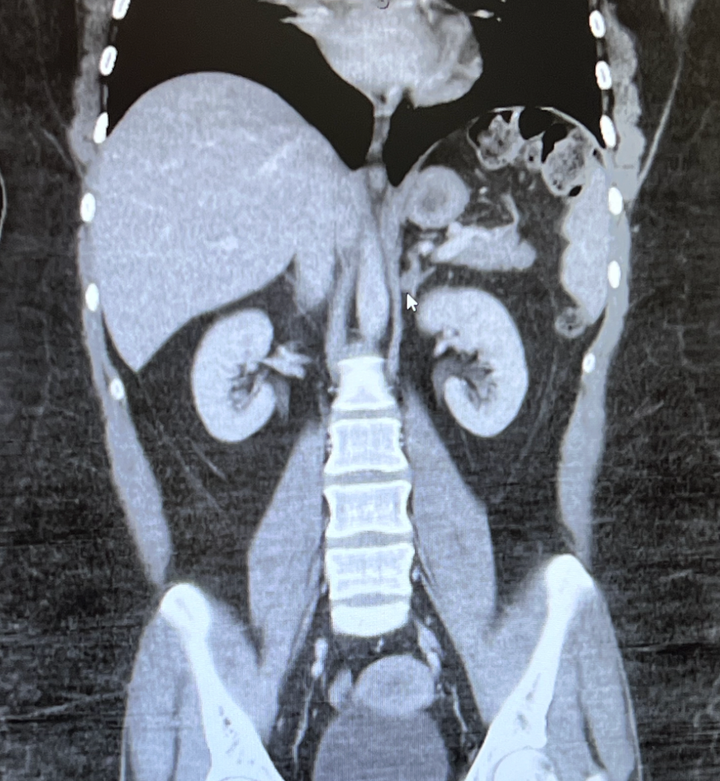

He was amazing, and he showed me the images. The mass looked like a fuzzy little mold spore sitting on top of my left kidney. My mom took pictures of the screen because she knew I’d want them. We talked about my symptoms, and he told me the agonizing episodes that sent me to the ER were likely kidney stones, a short-term complication of the effects of cortisol.

The surgeon said leaving the mass alone to keep overproducing hormones would be detrimental to my health in the long term, especially because I’m not even 30. The tumor was the size of a Skittle, but it could end up causing myriad problems, including heart attacks, blood clots, muscle weakness and broken bones.